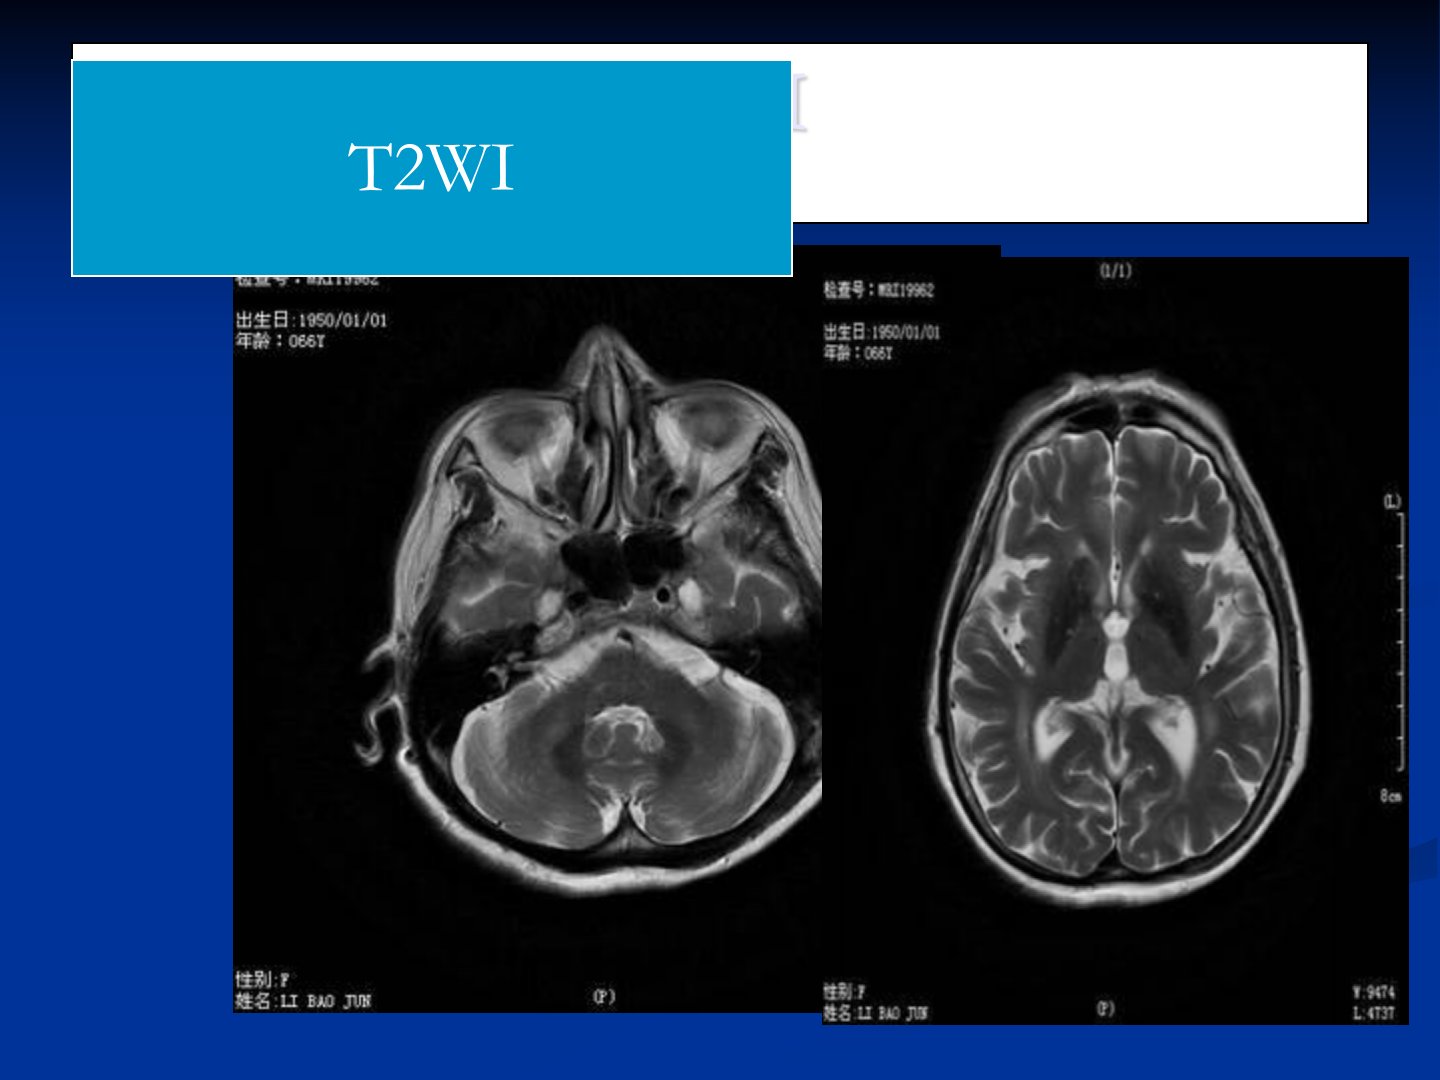

患者颅脑CT、MR显示双侧半卵圆中心、侧脑室旁多发点片状等、稍长T1稍长T2信号脑白质边缘见条状T1WI高信号双侧丘脑、小脑齿状核等多处见多发性对称性片状及条状T2低信号脑室略扩张脑沟、脑裂、脑池增宽加深结合CT观察上述部位均为对称性钙化灶筛窦、额窦粘膜增厚。讨论鉴别诊断包括:1Fahr病:特发性家族性脑血管亚铁钙沉着症病因不明有家族倾向。CT表现为双侧基底节、丘脑、小脑等多处高密度钙化常对称性多发形态多样内囊不受累病灶无强化。MR表现基底节、丘脑对称性钙化等。2结节性硬化:常染色体显性遗传的神经皮肤综合症病理特征主要为错构瘤结节好发于大脑皮层等1015易伴发室管膜下巨细胞型星形细胞瘤临床典型三联征为癫痫、智力低下和面部皮脂腺瘤。3正常颅内生理性钙化:需与上述病变进行鉴别。